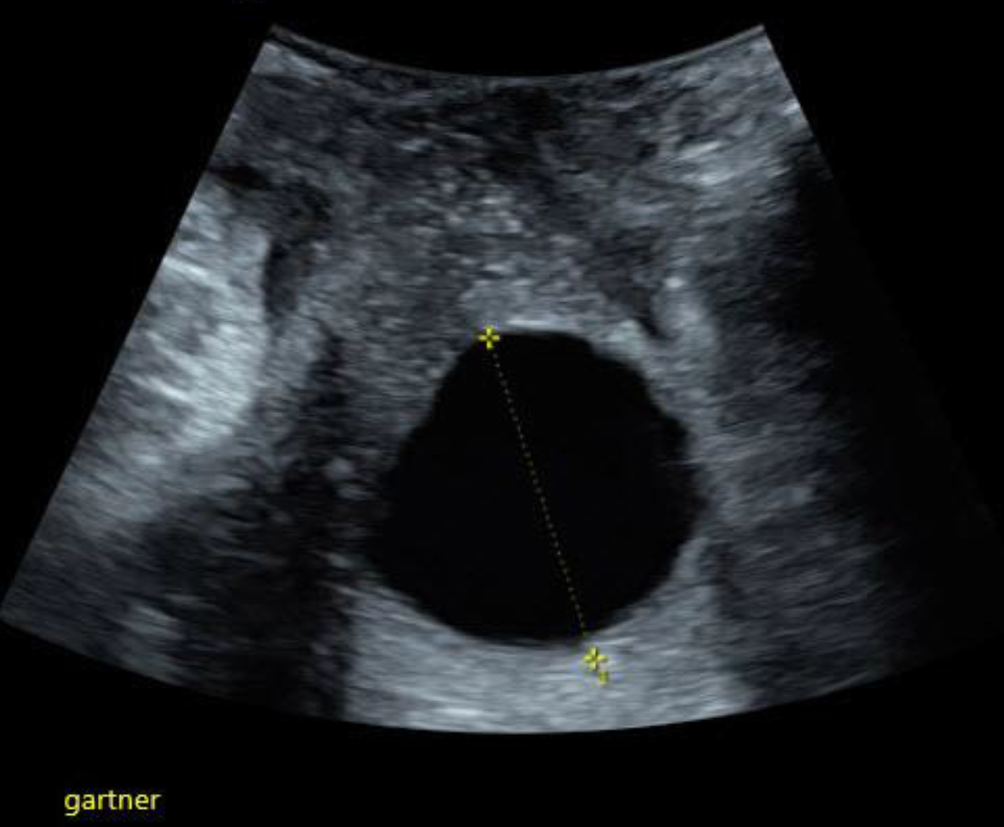

Abb. 5

Mit dem Abdominalschallkopf von perineal geschallte, seit 4 Jahren konstante Gartner-Gang-Zyste im Bereich des Fornix vaginae

Die Gartner-Gang-Zyste

Gartner-Gang-Zysten sind im Prinzip harmlos, das Innere der Zysten ist meist dünnflüssig, kann aber auch gallertartige Konsistenz haben [4]. Selten – und dann eher im jugendlichen Alter – können sie sehr groß werden [5]. Es gibt einzelne Fallberichte von malignen Prozessen im Vaginalbereich, die aus Gartner-Gang-Zysten entstanden sein sollen [6, 7]. Beobachten mittels Bildgebung ist bei symptomlosen Patientinnen einer Punktion oder Exzision auf jeden Fall vorzuziehen (Abb. 5 und 6).